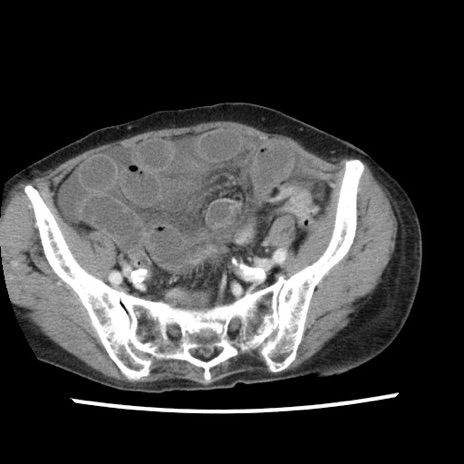

冠状断像

矢状断像